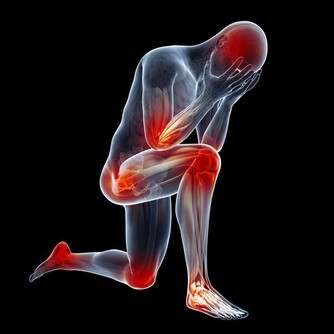

在你看來,打嗝除了讓自己感覺不大舒服之外,最大的後果也就是影響自身形象,可能讓自己看起來不太淑女,或者不夠紳士。其實這通常是件好事,讓你感到舒適,並表示你的消化系統正在發揮作用。

然而,如果你過度打嗝,這絕對值得關注。

如果你打嗝到令人煩惱的程度且每週出現三次及以上,就應該去看醫生了。

雖然打嗝幾乎不會是疾病的徵兆,但反复打嗝,尤其是與下列症狀一起發生時,可能意味著嚴重的健康問題。

3. 你的肋骨疼得厲害

食道裂孔疝是一種胃的一部分通過食管裂孔進入食道的疾病,可導致反复打嗝。就其本身而言,裂孔疝不是緊急情況,但它可能讓你非常不舒服。當疝氣切斷腹部其他部位的血液供應時,疝氣也會變得“絞亂”。這時候需要緊急手術,如果不及時治療後果可能是致命的。